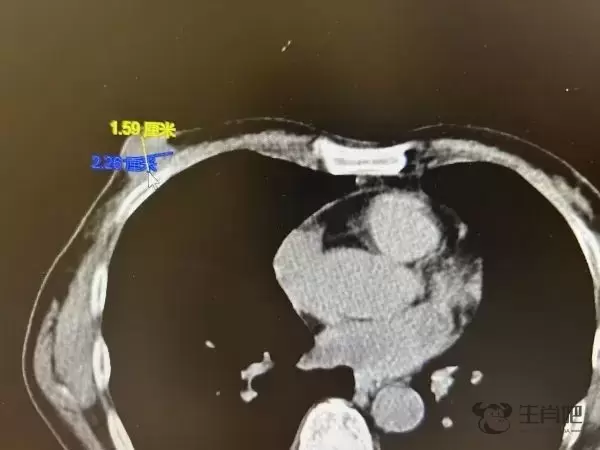

影像报告显示,张老伯的右乳有一个直径约为2厘米的肿块,初步诊断考虑为乳腺恶性肿瘤,如果不及时手术切除,可能会进一步进展转移。医生迅速为张老伯进行了乳房肿块切除活检手术,经快速病理检查,确诊是乳腺癌 。

影像报告显示张老伯的右乳有一个直径约为2厘米的乳腺恶性肿瘤